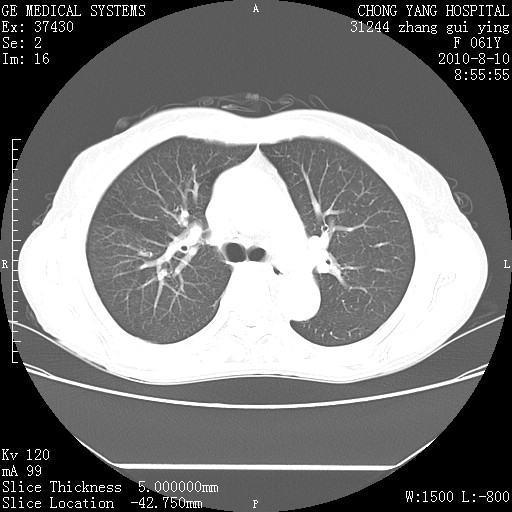

标题: CT28314:F61Y胸部增强,发热咳嗽一周入院,后面的为一周前平 [打印本页]

标题: CT28314:F61Y胸部增强,发热咳嗽一周入院,后面的为一周前平

1、支持考虑右侧中央型肺癌伴右肺中叶节段性不张及下叶支气管黏液痰栓    2、左肺上叶舌段感染。

支持右下肺中央型肺癌并左上肺感染.

我也觉得右肺中叶支气管受累

确切的说:1:右肺下叶中心型肺癌侵及中叶支气管并中叶不张,纵膈淋巴结转移。2:左肺舌叶炎症。3:右侧胸腔少量积液